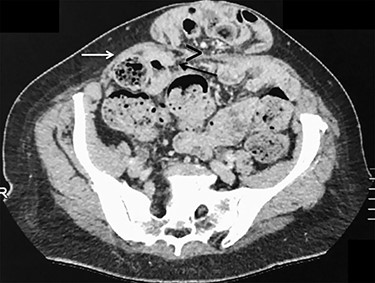

Axial view of contrast-enhanced CT scan showing a small opening (>) with ascending protrusion of bowel between the posterior rectus sheath (black arrow) and the rectus muscle (white arrow).

ALH is a peculiar type of interstitial parietal hernia of the anterior abdominal wall subdivided into three types [5] and more commonly identified in man, with a sex ratio difference of 12.5:1. One explanation is that more than a third of females don’t have a defined arcuate line, whereas most males do [6]. ALH rarely causes symptoms, as the hernia orifice is wide and can be easily mistaken as a Spigelian hernia on preoperative imaging that explains the number of cases only being diagnosed at laparoscopy [7]. Similarly, in our case, only the ventral hernia was clinically obvious and the bilateral ALHs were incidentally detected during laparoscopy. This reinforces the superiority of laparoscopy that allows us, alike in groin hernia surgery, to detect and simultaneously repair any coexistent defects [8]. Anecdotally, further re-examination of the preoperative CT-scan could probably reveal ascending protrusion of bowel between the right posterior rectus sheath and rectus muscle (Fig. 6).